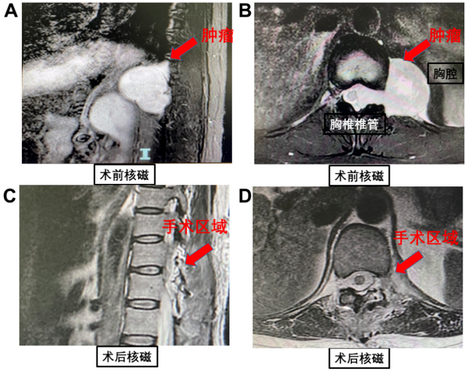

50岁的李阿姨因左侧后背及下肢疼痛1年,来到我院神经外科就诊。胸椎核磁显示,一个5厘米大小的哑铃型肿瘤存在于李阿姨的椎管内及左侧椎管外。肿瘤血供丰富,导致脊髓受压右移,且左侧椎间孔扩大,肿瘤突入胸腔膈肌上。此前患者曾转诊多家医院,但都因手术风险极高而没有被收治。由于疼痛难忍,患者带着最后一线希望找到了北京积水潭医院神经外科主任苏亦兵。

对患者的病情进行全面评估并与患者及家属充分地沟通病情后,专家们制定了最终的手术方案。手术过程分为两场,神经外科先由后方入路切除胸椎椎管内的肿瘤,断其基底减少供血;后由胸外科进行胸腔镜下手术切除胸腔内肿瘤的剩余部分。在麻醉科、手术室和ICU医护人员的保驾护航下,神经外科联合胸外科通过一台手术的“上下场”分工,一气呵成,完整地切除了患者的巨大肿瘤。目前患者各方面情况良好,症状缓解明显,将于近日痊愈出院。